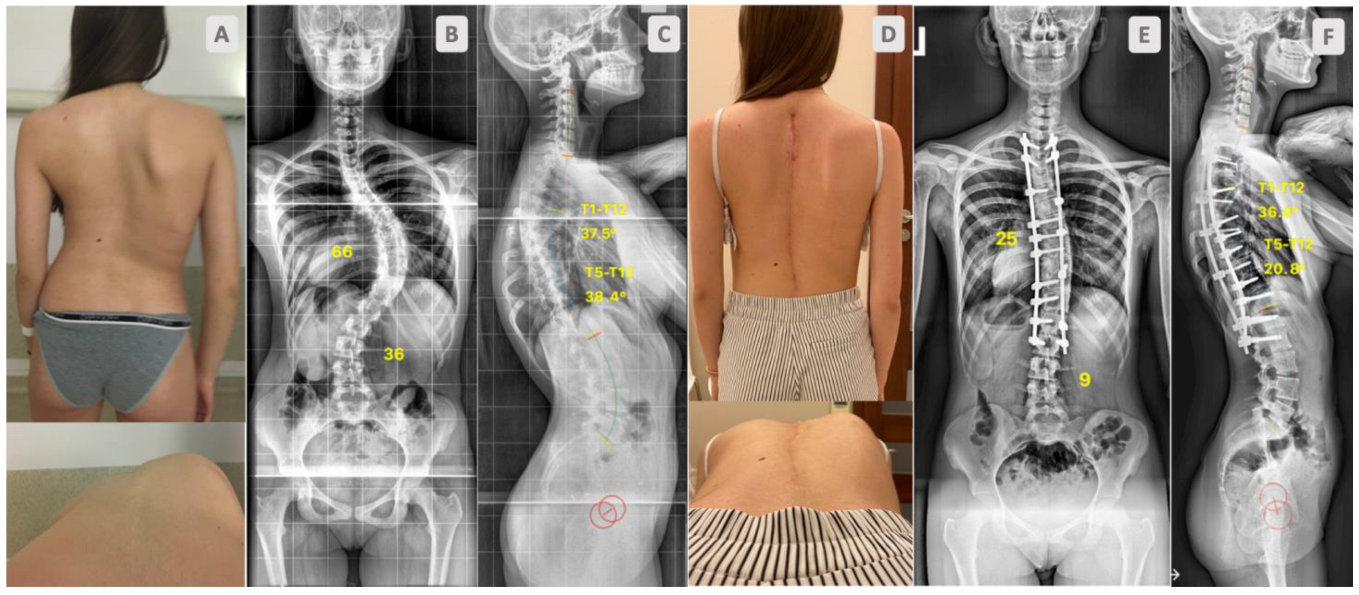

2. Material and Methods

3. Results